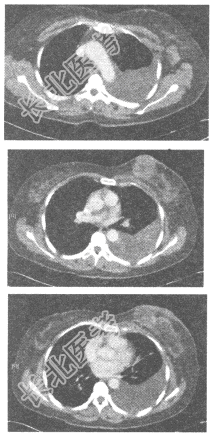

- 单项选择题患者,女性, 56岁,胸部CT发现乳腺占位性病变, 图像如下,以下对该患者乳腺病变较精确的诊断应为

A、乳腺癌

B、乳腺癌,并腋窝淋巴结转移可能性大

C、乳腺纤维腺瘤

D、乳腺炎

E、乳腺囊肿